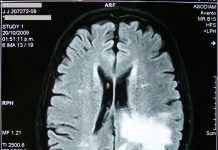

Extending the reach of MRI with new portable brain imaging scanner

A new low-cost, compact, portable, and low-power brain imaging scanner has been developed.

The new device, which has been developed by a team at Massachusetts...